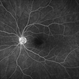

- toxic maculopathy

Clarus 700 - Description

- A 50-year-old woman with a 15 year history of pentosan polysulfate treatment for interstitial cystitis.